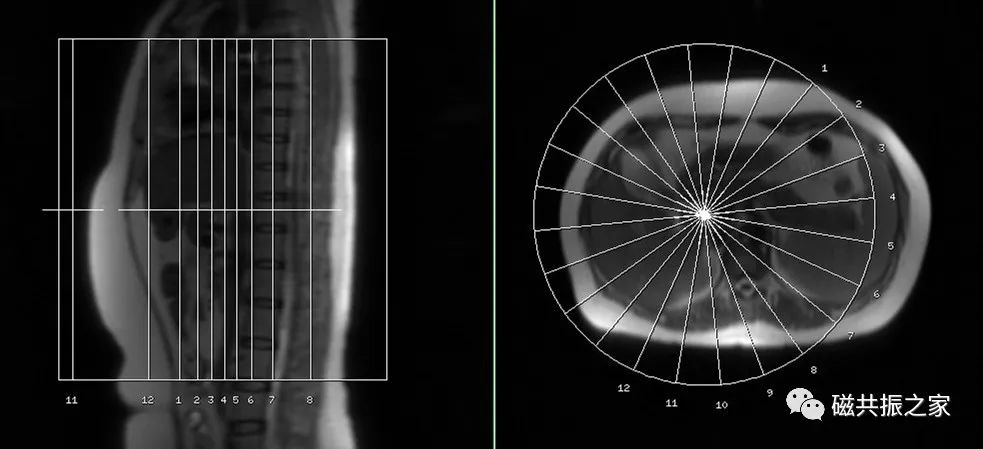

厚模块2D MRCP序列

主要在横轴位上定位,采用厚层模块扫描,采用放射状的定位方式;并在冠状和矢状位上调整FOV的上下位置。

呼吸触发或屏气的薄层冠状面3D MRCP序列

在横轴位和矢状位上定位,定位与主胰管走形一致,如需了解肝内胆管情况可与肝内胆管走形定位扫描。扫描范围包括肝管、胆管、胆囊、胰管,合理调整扫描范围,需包括整个病变范围。

3D MRCP模块扫描范围尽量不要包括前腹部,同时添加相应的饱和带,可以有效的改善前腹部呼吸运动带来的伪影。同时扫描模块能避开主动脉的尽可能避开主动脉区域。